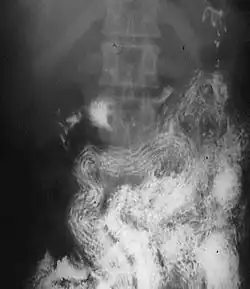

![]() | |

| Ascaris worms (one type of helminth) in the small bowel of an infected person (X-ray image with barium as contrast medium) | |